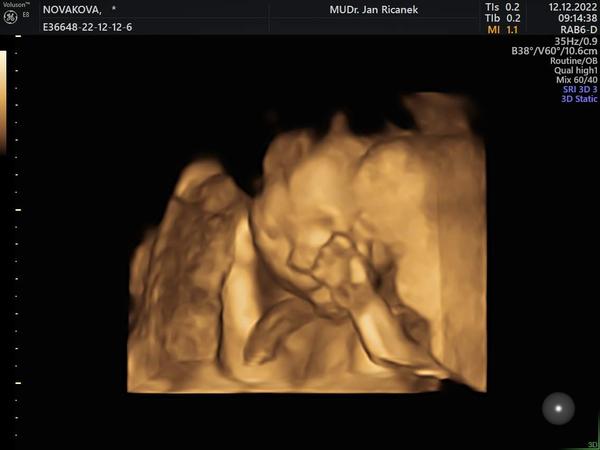

Tak holky dnes 2. trimestralni screening a vse v poradku 🙂 <3

Já mám taky hezkou fotku z poslední kontroly 🤣🤣🤣 má krásnou páteř